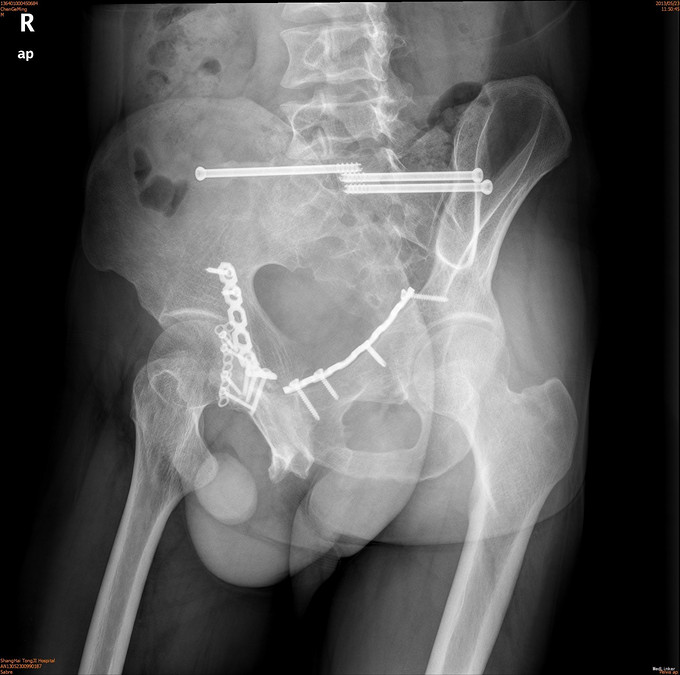

诊断为耻骨上下支骨折,兄弟科室会诊治疗结束后,患者病情稳定,行切开复位内固定术。

1年后随访患者无疼痛,活动可。耻骨上下支骨折ORIF术疗效良好。